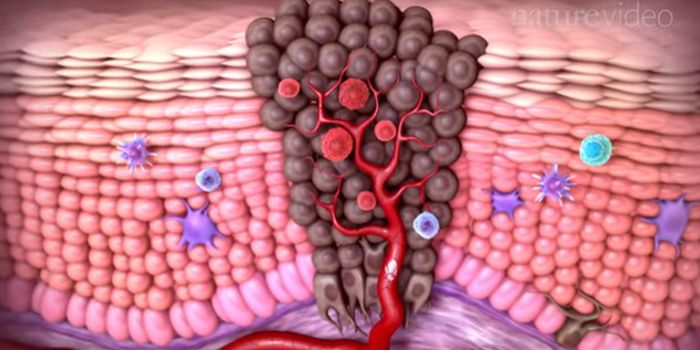

MAY 05, 2016VideosCancer spreads by the process of metastasis, where malignant cells break off from tumors in one part of the body and tra ...